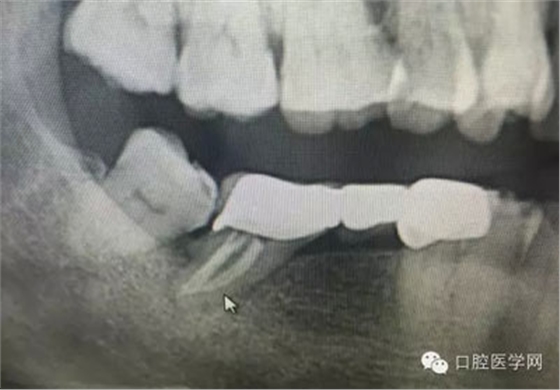

根管再治療是我們比較頭疼的,尤其是那些冠修復(fù)過的,我們有很多的麻煩需要去溝通,比如可能導(dǎo)致的側(cè)穿、可能沒有看到的腐質(zhì)、可能導(dǎo)致的崩瓷,或者是后期可能出現(xiàn)冠折......這些需要我們和患者好好的溝通。全瓷冠還好些,金屬冠根測(cè)的時(shí)候很是麻煩,總之我們做修復(fù)的時(shí)候不要單純的追求速度,追求效益,適當(dāng)?shù)淖⒁庀挛覀兊幕A(chǔ)治療和設(shè)計(jì)。

這是一例外院樹脂修復(fù)后十個(gè)月出現(xiàn)牙髓炎癥狀的患者。遇到這樣子的患者大家會(huì)怎么做,證明選擇,還有就是可做可不做治療的如何去平衡。